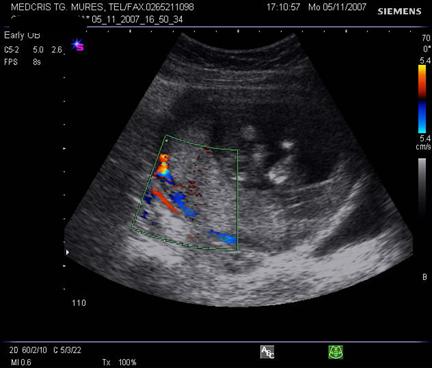

Arterele spiralate si placentomul. Dupa 28 sapt. mici ecouri anecogene rotunde apar in substanta placentara, reprezentand centrul placentomului - mica unitate de flux, unde se deschid artere spiralate. Cu ajutorul Doppler-ului color se poate urmari ejectia sangelui din arterele spiralate.

Fig. nr.222. Hematom

la nivelul placii deciduale a

placentatiei la 10 sapt. , cu intreruperea vascularizatiei la Doppler color (

sageata ). Se remarca vascularizatia cordonului ombilical si insertia centrala

a acestuia in placenta